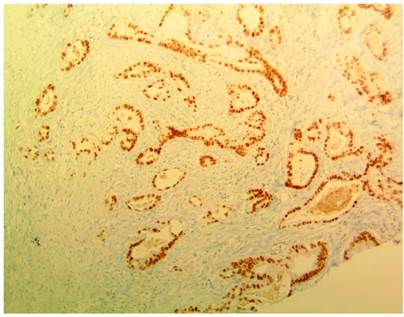

En hospital de remisión requirió manejo con apendicectomía laparoscópica y derivación de vía biliar por colangiopancreatografía retrógrada endoscópica, con inserción de un stent biliar. Hallazgo intraquirúrgico de un plastrón apendicular, abundante líquido peritoneal cetrino, estrechez del conducto hepático común, con sospecha de compromiso neoplásico. Se trasladó al Hospital Militar Central en Bogotá, Colombia, para continuar con manejo integral. Se documentó síndrome biliar obstructivo, con recuento de bilirrubina total de 3,02 mg/dL, bilirrubina directa de 2,71 mg/dL, fosfatasa alcalina de 1006 UI/L, alanina aminotransferasa (ALT) de 149 U/L y aspartato aminotransferasa (AST) de 139 U/L. Los hallazgos de la colangiorresonancia se exponen en la Figura 1 y los de la tomografía axial computarizada (TAC) en la Figura 2. El resultado de la biopsia apendicular evidenció compromiso por adenocarcinoma moderadamente diferenciado de serosa y capa muscular (Figura 3), con inmunohistoquímica positiva para anticuerpos CK7, EMA, CEA monoclonal y CDX2 (Figura 4), que sugirió origen extraapendicular, probablemente de tracto gastrointestinal superior o hepatobiliar.